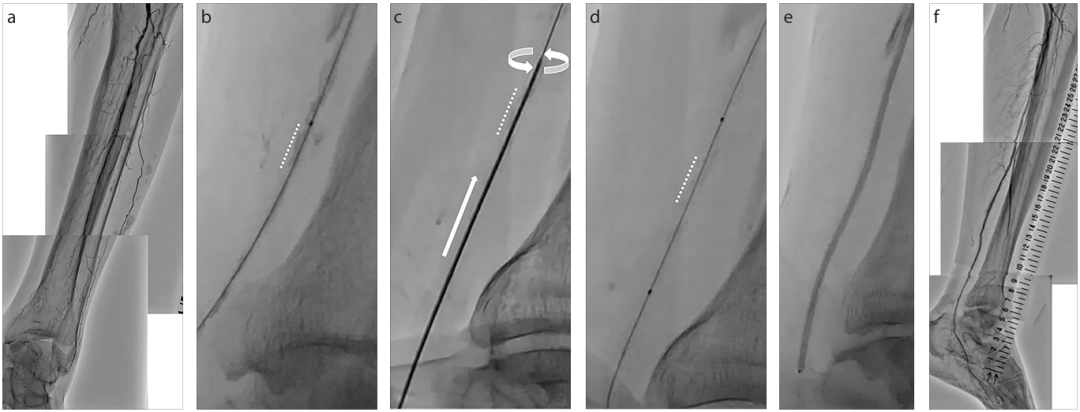

a、b. 内PIERCE技术示意图。图a显示,通过建立顺行入路部位与远端穿刺部位之间的导丝外置化,或通过顺行球囊导管在钙化病变近端锚定逆行导丝,实施远端BTK或BTA穿刺的双向入路。图b显示,从远端穿刺部位沿导丝将20G穿刺针置入动脉内,小心地边旋转边推进20G穿刺针,数次穿过钙化病变。

a–f. 器械输送困难的代表性病例。术前血管造影(a)显示胫后动脉(PTA)长段慢性完全闭塞(CTO)。图b显示,从PTA远端的逆行导丝穿过CTO病变并被外置化。低剖面球囊导管无法穿过钙化病变(虚线)。图c显示内PIERCE技术。图d显示低剖面球囊穿过并扩张钙化病变。图e显示通过长球囊导管实现充分的病变扩张。最终血管造影(f)显示PTA成功重建血运。